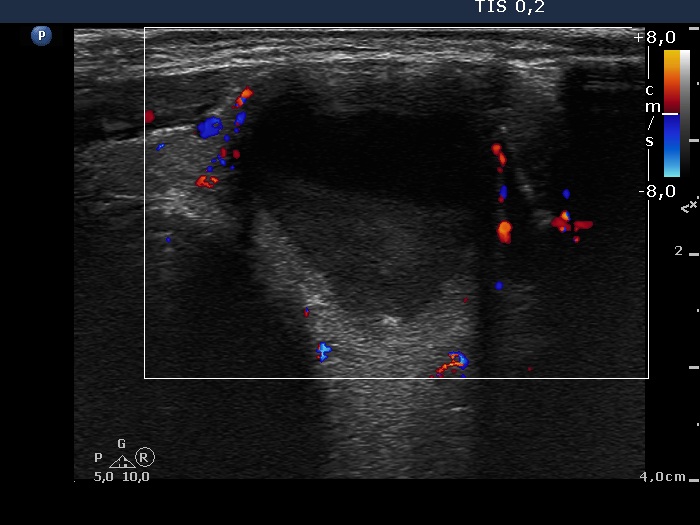

Consecutively operated patients with autoimmune thyroid disease - case 65 (1629) (ultrasonographic picture 6)

Isthmus, transverse scan, color Doppler mode. The vascularity is non-specific.